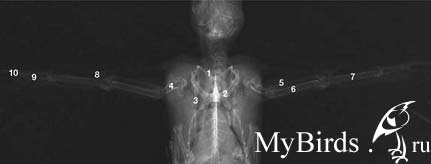

Нормальная анатомия скелета взрослого черного стрижа (плечевой пояс и крылья): 1) ключица, 2) клювовидный отросток, 3) лопатка, 4) плечевая кость, 5) лучевая кость, 6) локтевая кость, 7) пястно-запястная кость или пряжка, 8) фаланга придаточного крылышка , 9) короткая трубчатая кость и 10) дистальная фаланга большого пальца